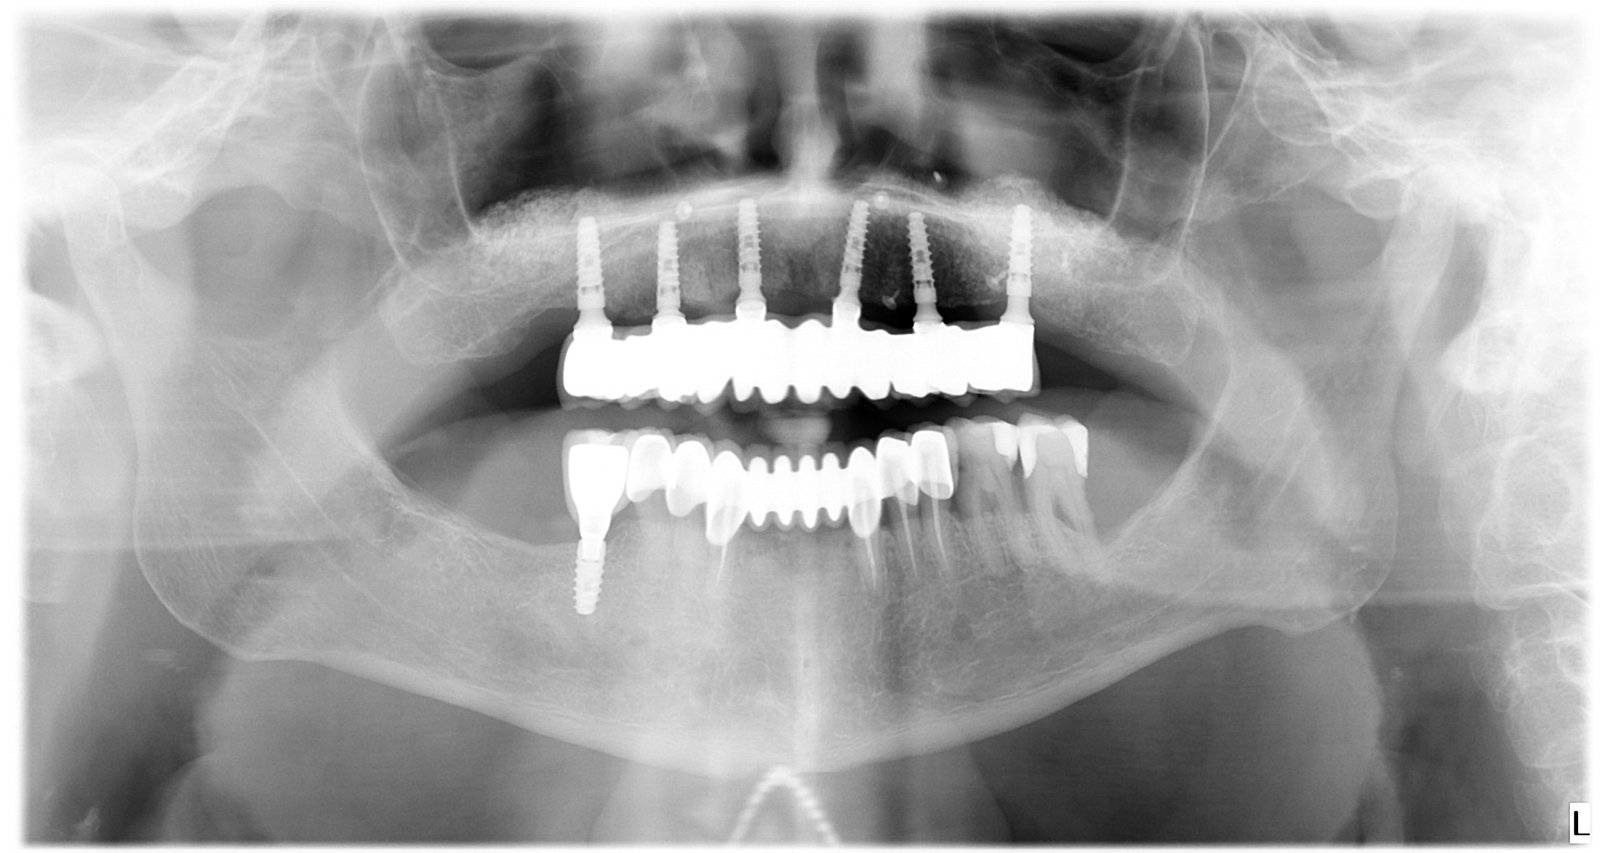

Caso 2 - caso de Implantes dentales

El paciente presentaba pérdidas dentales que comprometían tanto la función como la estabilidad de su mordida. Mediante un tratamiento con implantes personalizados logramos restablecer una dentadura fija, estable y adaptada a su anatomía.

Se observa la colocación de los implantes en la posición óptima, garantizando una base sólida para la posterior rehabilitación protésica.

La radiografía final confirma la correcta integración de los implantes, asegurando una solución duradera y completamente funcional.